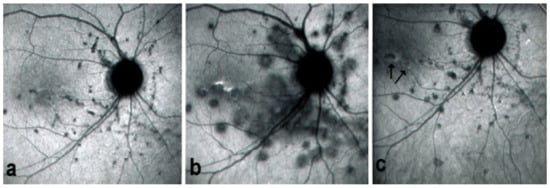

On fundus examination, the typical lesions are small randomly distributed choroidal mostly atrophic yellow-white foci with pigment spots (Figure 13) that sometimes can become adjacent to each other and form a ribbon of pearls. These lesions involve the posterior pole, around the disc, as well as the mid-periphery. In the active phases of disease, new lesions are not always visible and can be very discreet on FA, whereas ICGA is the most sensitive method to detect new lesions, as is the case in MEWDS [30,37,53,54,55]. (Figure 14) One particular feature of multifocal choroiditis is the high proportion of choroidal neovascular membranes complicating the disease, occurring in as much as one-third of cases.

As for all PICCPs, multimodal imaging is best accounting for MFC features (Table 4). On ICGA, the first set of signs identifies old scarred chorioretinal lesions and consists of hypofluorescent areas persisting up to the late angiographic phase, distributed at random in the fundus, corresponding to late hyperfluorescence on FA, typical for chorioretinal atrophy from scars of previous inflammatory episodes seen on colour fundus photos. The second set of signs can be seen in addition to the previously described signs when choroiditis recurs or can be seen in the absence of scars when it is the first episode. The signs consist of hypofluorescent areas, either silent on fluorescein angiography or hyperfluorescent in the late phase and usually not visible on fundus examination, representing areas of new inflammatory involvement (Figure 14). As in many PICCPs, some cases may present peripapillary hypofluorescence, translating functionally into an enlarged blind spot [18,36,54,55] (Figure 15). The hypofluorescent areas can completely regress if inflammation suppressive treatment is started promptly. In a substantial proportion of cases, the extent of ICGA hypofluorescence reflecting choriocapillaris hypoperfusion or nonperfusion is far more widespread than visible lesions let suspect, showing widespread areas of late occult hypofluorescence with absolutely no signs visible on fundus examination or on fluorescein angiography (Figure 15).